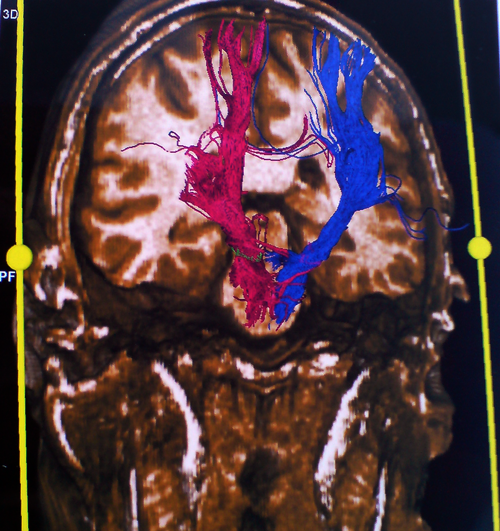

Στο μοντέλο αυτό μπορούν να συνεισαχθούν και πληροφορίες από άλλες ακολουθίες της μαγνητικής τομογραφίας, π.χ. λειτουργικές ακολουθίες όπου απεικονίζονται θέσεις κέντρων του λόγου ή της κίνησης ή ακολουθίες δεσμιδογραφίας όπου απεικονίζονται νευρικές οδοί στο βάθος του εγκεφάλου. Ο χειρουργός έχει έτσι την δυνατότητα να σχεδιάσει προεγχειρητικά την επέμβαση, αποφεύγοντας για παράδειγμα προσπελάσεις που αυξάνουν τον κίνδυνο τραυματισμού ευγενών περιοχών του εγκεφάλου ή μεγάλων αγγείων. Η ταύτιση του ψηφιακού μοντέλου με τον προεγχειρητικό σχεδιασμό και της πραγματικής ανατομίας γίνεται στο χειρουργείο με την |

Δεσμιδογραφία (DT MRI) εγκεφάλου |